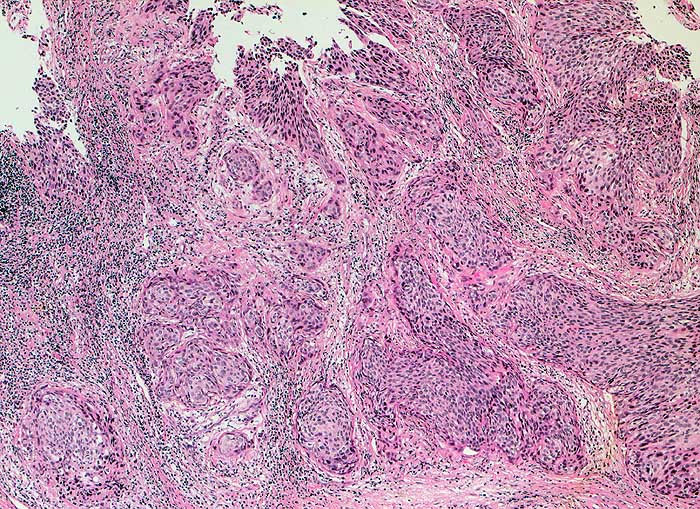

g/ Plattenepithelkarzinom der Zervix

Plattenepithelkarzinom der Zervix

Die Tumorzellen liegen einzeln oder in kleinen Verbänden und ganzen Gewebsfragmenten. Die polymorphen Kerne sind vergrössert und enthalten verklumptes unregelmässig verteiltes Chromatin und grosse Nukleolen. Gut differenzierte Karzinome erkennt man am breiten und oft verhornten Zytoplasma. Längliche bis fadenförmige Tumorzellen mit pyknotischen Kernen können als einziger Hinweis auf das Vorliegen eines Karzinoms vorhanden sein. Wenig differenzierte Karzinome haben polymorphe und schlechter erhaltene Kerne. Der Hintergrund ist meist detritisch und oft hämorrhagisch. Ulzeration, Einblutungen und bakterielle Infektionen beeinflussen den Erhaltungszustand und die Art der abgestrichenen Zellen. Ist die Oberfläche eines ulzerierten Karzinoms von einem Fibrinschorf bedeckt, enthalten die Ausstriche lediglich Detritus, Granulozyten und Erythrozyten, aber keine Tumorzellen. Die Sensitivität für die Karzinomdiagnose ist aus diesem Grund geringer als für die Diagnose eines Carcinoma in situ.